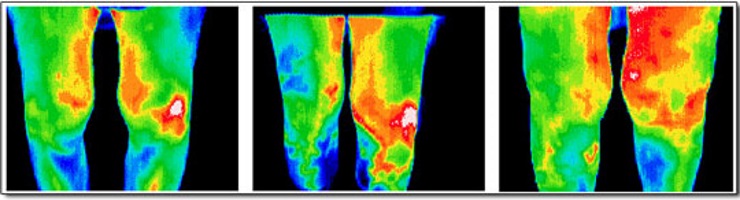

Ефективність передопераційної діагностики з використанням КТ-ангіографії при реконструктивних втручаннях на нижніх кінцівках

Авторы: С. В. Слєсаренко, П. О. Бадюл, С. О. Мунтян, К. С. Слєсаренко, О. О. Ковбаса Статья опубликована в журнале: Клін. хірургія. – 2016. – № …